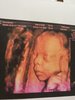

Moj przystojniak Oskar [emoji173][emoji173]

I fiutek na ostatnim zdjęciu [emoji7][emoji23]

1528969282629.jpg

1528969314660.jpg

1528969334089.jpg

1528969345451.jpg

Załączniki

• 1528969282629.jpg

461,4 KB · Wyświetleń: 452

• 1528969314660.jpg

593,8 KB · Wyświetleń: 440

• 1528969334089.jpg

554,2 KB · Wyświetleń: 436

• 1528969345451.jpg

761,4 KB · Wyświetleń: 455